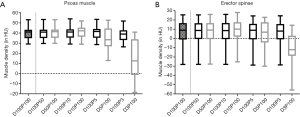

Mean MD was 6.41±13.55 HU for the erector spinae muscles derived from original dose images (D100P100). Sparse sampling derived mean MD showed no significant changes (P=0.57) down to 5% of the original projections (D100P5). For the psoas muscle, mean MD amounted 39.86±6.14 HU. No significant changes in mean MD of the psoas muscle were observed down to D100P5 (P=0.22) (Table 2 and Figure 2). Representative images of virtually lowered tube current and sparse sampling are shown in Figure 2.

The virtual tube lowering showed no significant (P>0.05) changes for the mean MD of the erector spinae at 5% of the original dose D5P100 (P=0.19) as compared to D100P100. However, mean MD derived from D50P100, D10P100 and D3P100 were significantly different as compared to D100P100 (P<0.01). In the psoas muscle, all virtually reduced tube current series showed significantly different mean MD as compared to the original dose.

The comparison of corresponding sparse sampling and virtually tube reduced series (D100P50/D50P100, D100P10/D10P100, D100P5/D5P100 and D100P3/D3P100) is shown in Table 3. The 50% and 10% reduced series of the psoas and the 5% reduced series of the erector spinae MD did not differ significantly from each other (P>0.05) (Figure 3).

The Signal-to-noise ratio (SNR) for each virtually tube reduced series is shown in Table 4. In the erector spinae the SNR did not reveal significant differences for the sparse sampling series down to 5% (D100P5) of the original dose (P=0.08). A high ICC was given between the two readers in both muscle compartments (ICC =0.98, P<0.01).